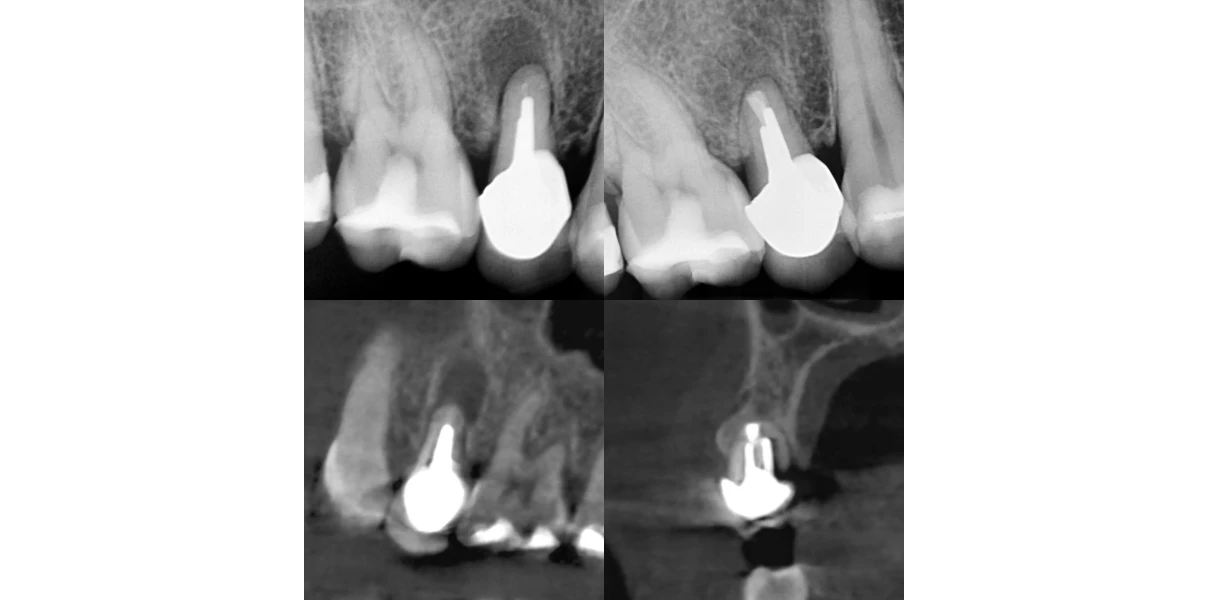

Chirurgie endodontique

Retraitement

Instruments fracturés